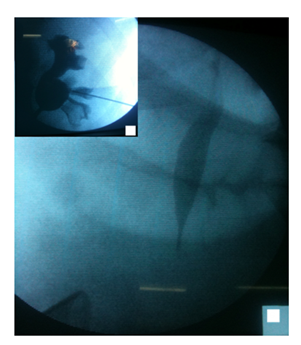

All procedures were carried out under general anesthesia. The patient was placed in the modified supine position. The flank is elevated 30 to 45° with regard to horizontal plane and lower limbs are split and bent in a lower position (Figure 1). The retrograde approach was used initially in all cases. If unsuccessful (Failure to find ureteric orifice or Failure to cross stricture), antegrade or both antegrade and retrograde approach was attempted. The most accessible posterior calyx was punctured under ultrasound guidance using a 22G Chiba needle and the tract dilated to 10 Fr. Radiopaque contrast and Methylene blue were injected into the renal cavity. The renal pelvis, Pelviureteric junction and calyces were identified as the seat and length of the stricture (Figures 2A & 2B). Once the pelviureteric junction was crossed and the ureter accessed, a straight hydrophilic guide wire and a special intrarenal manipulation catheter were used to cross the malignant ureteric stricture (Figure 3). If the stenosis was too tight and that the guide failed to pass, a resection guided with fluoroscopy in the direction of the guide was performed in the same flank modified position. The resection was continued until visualization of the guide and Methylene blue.

Figure 3 A straight hydrophilic guide wire and a special intra-renal manipulation catheter were used to cross the malignant ureteric stricture.